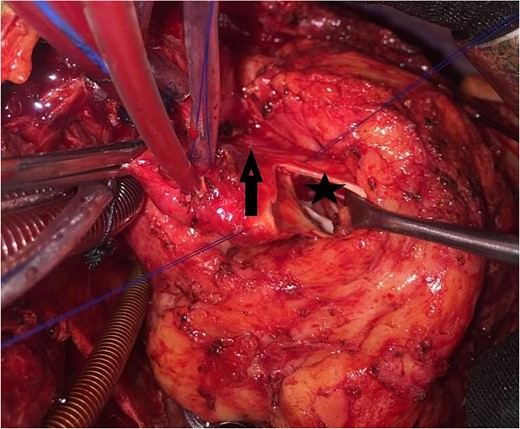

An 11-year-old girl was referred to our hospital with a main complaint of progressive exertional dyspnea. She had undergone surgical repair of SAS 6 years ago. Transthoracic echocardiogram (TTE) revealed the following findings: severe left ventricular hypertrophy, tunnel-like fibromembranous subaortic stenosis with a length of 10 mm, a peak gradient (PG) across the LVOT of 170 mmHg, and mild aortic regurgitation. Based on these findings, the patient was scheduled for elective surgical repair with a possible indication for MKO. The operation was performed via median sternotomy with great caution to avoid inadvertent rupture of any cardiac cavity due to heavy adhesions from the previous operation. The aorta was cannulated just below the takeoff of the innominate artery. Bicaval cannulation was performed to provide a bloodless field. Aortic cross-clamping was applied, and antegrade cold blood cardioplegic solution was administered via a catheter placed in the ascending aorta. The ascending aorta was opened transversely 1 cm above the sinotubular junction (Fig. 1). The aortic valve leaflets were examined carefully to confirm that the aortic valve could be preserved. LVOT was examined thoroughly, and it was clear that the stenosis in the subaortic area was so complex that simple resection through the aortic valve orifice would not be sufficient. The right ventricular outflow tract was opened transversely below the pulmonary valve. The conal papillary muscle was identified (Fig. 2). A right-angle instrument was introduced through the aortic orifice into the interventricular septum, and the tip of the instrument was used to perforate the conal septum to the left of the conal papillary muscle to prevent damage to the conduction system; the septal incision was completed with great caution to avoid damage to the aortic cusps and to extend the incision downward as necessary to completely relieve the stenotic subaortic area (Fig. 3). Interrupted 5/0 Prolene sutures were placed circumferentially around the septal incision to close the interventricular septal defect using a bovine pericardial patch to provide adequate widening of LVOT (Fig. 4). The right ventriculotomy was closed with a second bovine pericardial patch to avoid any possible obstruction of the right ventricular outflow tract (Fig. 5). The remainder of the operation was completed uneventfully. After 6 hours of mechanical ventilation, the patient was extubated, and she convalesced well postoperatively. TTE showed excellent results of the operation with PG across LVOT of 20 mmHg. On 1 year follow-up, the patient was asymptomatic and in very good general condition, and TTE findings confirmed the excellent result.

Intraoperative image showing the right ventriculotomy (2) and the conal papillary muscle (1).